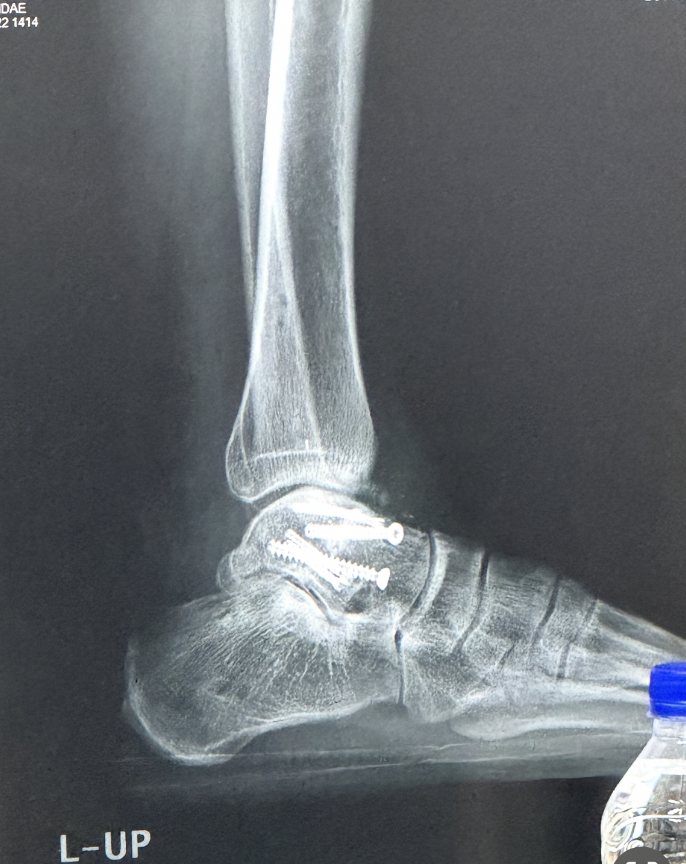

의사 선생님이 CT와 X-ray로 검진을 하자고 했다. CT와 X-ray촬영 후 다시 검진을 받았다. 의사 선생님의 소견은 이전과는 달랐다. 나는 가장 불편한 것이 발목이 수직이 아닌 상태로 굳어져 발을 딧지 않다가 딛으려고 할 때 절 수밖에 없다는 것이라고 했다. 의선생님은 그 부분은 조금씩 나아지고 있으니 좀 지켜보자고 하셨다.

거골이 완전히 매끄럽게 붙지 않아서 표면이 거칠다고 했다. 지금은 연골이 중간에 있어서 괜찮지만 조금이라도 문제가 생기면 재수술을 할 수도 있다고 하셨다. 그러고는 될 수 있으면 발을 앞으로 꺾는 운동이나 지속적으로 발 앞복으로 체중을 싣는 행동을 하지 말라고 하셨다. 아직 달리응 것이 서툴러서 연습을 하고 있었는데 이것도 중단해야 했다.

내 나이가 아직 젊고 발을 쓸 시간이 많이 남아있기 때문에 최대한 아껴 쓰길 바라 신 것 같다. 평소에는 잊고 있다가 다시 검진날이 되어 설명을 들으니 더 조심해야겠다는 생각이 들었다. 지금이야 부모님이 계셔서 나에게 문제가 생겨도 케어를 해줄 수 있지만, 더 나이가 들고 그때 문제가 생기면 어떻게 될지 모르는 일이다.